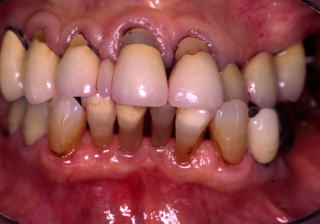

■症例:歯周病と歯科治療恐怖症(図4−8)

患者:63歳、女性、 週刊朝日(2006年6月)掲載症例。

診断および治療過程:当院で局所麻酔薬の皮内反応を調べた結果、シタネストのみ使用可能であった。しかし、患者は外科手術を極度に拒否したため、麻酔をまったく使用せず、治療は盲嚢掻爬とDiathermyに頼らざるを得なかった。

歯周膿瘍を頻発していた歯周組織がここまで回復した(図4−8)。

歯周治療の分野での外科的Diathermyは、誘電加熱(80−90℃)によるポケット内の静菌効果が主であるが、出力の調整次第では無麻酔科でCrettageと同等の処置も可能である。さらに、環境因子が整えばLong Waveによる骨芽細胞の活性化の可能性も推測された。